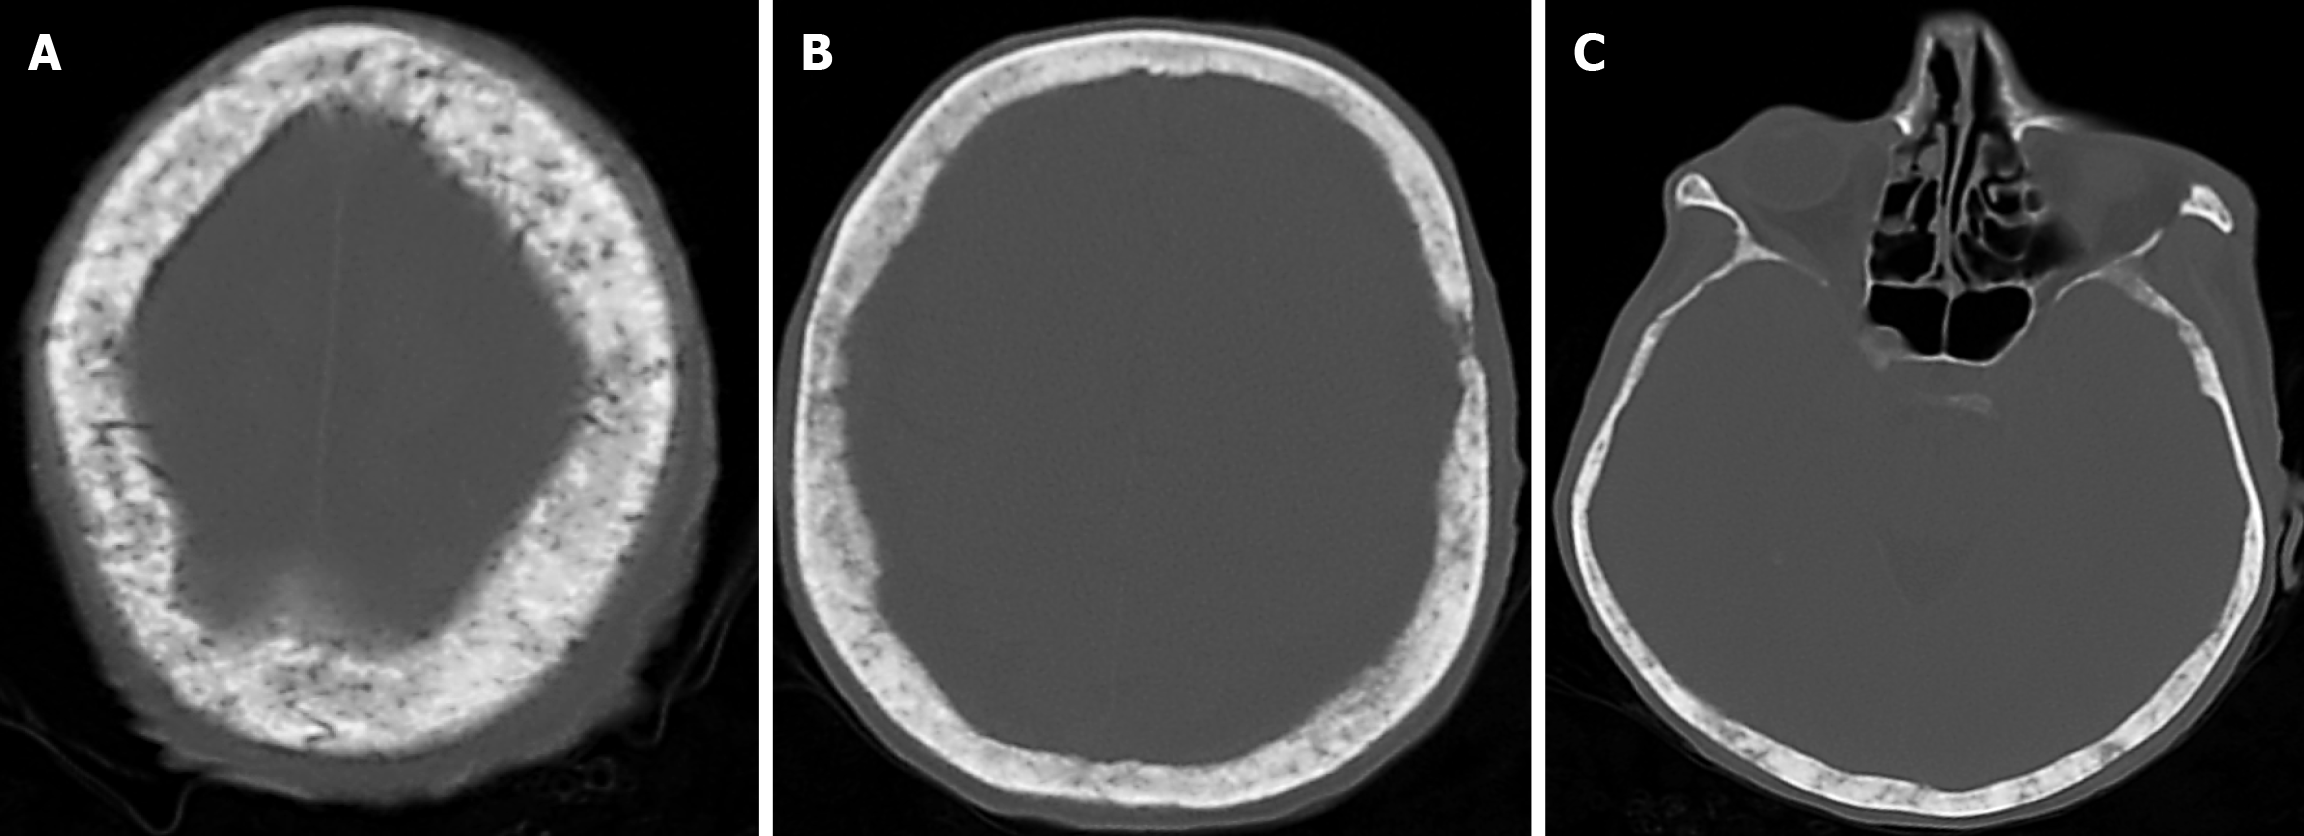

Arachnoid granulations (Pacchionian granulations) are cerebrospinal fluid-filled projections that extend from the subarachnoid space through openings in the dura into the venous sinuses and can be seen macroscopically. Their incidence varies from 0.3% to 55%. Arachnoid granulations are usually seen in millimeter dimensions, but may grow to fill the dural sinuses or arch the inner table[11]. In addition, intraosseous arachnoid granulations can sometimes extend to the inner table of the bone, causing scalloping, remodeling or bone erosion of the inner table[12]. The prevalence of arachnoid granulations increases with age, but there is no difference in gender distribution. Arachnoid granulations with a slight left hemispheric predominance are found in the dural venous sinuses, most frequently in the transverse sinuses and especially in the middle or lateral parts. The second most common location is the superior sagittal sinus, but they can be found anywhere in the dural venous sinuses. Arachnoid granulations are usually detected incidentally. If they fill and expand the dural sinuses, causing partial sinus obstruction, they may cause symptoms of increased intracranial pressure due to venous hypertension. They are usually associated with headaches. Arachnoid granulations may be seen as radiolucent areas on plain radiography of the skull or may cause compression on the inner table of the skull. On CT imaging, arachnoid granulations can be seen as sharply demarcated, hypodense structures in close relation to the dural venous sinus. On MRI, they usually show hyperintense signal on T2-weighted images and hypointense or isointense signal on T1-weighted images compared to brain parenchyma (Figure 1). On CT angiography, MR angiography or catheter angiography imaging, arachnoid granulations appear as oval or round filling defects in the dural venous sinuses during the venous phase[11]. Recent advances in radiology have made it possible to identify brain herniations into the arachnoid granulation by improving image quality with higher resolution and thinner slice three-dimensional T1-weighted and T2-weighted MRI sequences (Figure 2). Brain herniation into the arachnoid granulation is rare in the literature, and the incidence of brain herniation into the calvarial or dural sinuses has been reported to be 0.32%[13]. Arachnoid granulations may be confused with pathological processes in the dural venous sinuses[11]. In the differential diagnosis of arachnoid granulations, venous sinus thrombosis, dural-based tumors, or structures such as septa and fat that may cause filling defects in the dural venous sinuses should be considered[12]. Dural sinus thrombosis usually fills an entire sinus segment or several sinuses and may extend to the cortical veins, whereas arachnoid granulations appear as focal and well-defined defects. Fresh thrombus in the dural sinuses are hyperdense on CT and hyperintense on T1-weighted MRI. Differential tumor diagnosis can be made based on its shape, lack of contrast enhancement and diffusion restriction[11].

The transcalvarial venous channels are the openings in the calvarium that connect the dural venous sinuses to the extracranial veins via emissary veins. They are usually seen as serpentine or linear lucencies with sclerotic margins along the skull, and when these vessels are dilated they are known as venous lakes. Venous lakes are sometimes confused with fractures or sutures[14]. Venous lakes are present in about 15% of patients and are not associated with age or gender[15]. Venous lakes appear on CT as round or oval lucencies at the level of the skull base (Figure 3). On MRI, they show medium or low signal intensity on T1-weighted images, high signal on T2-weighted images, and significant contrast enhancement is seen in contrast-enhanced series[14]. It is important to distinguish venous structures from metastases. Metastases often show restricted diffusion within the lesion due to high cellularity. In addition, metastases may show increased blood flow within the lesion. Metastases often invade adjacent tissues[15].